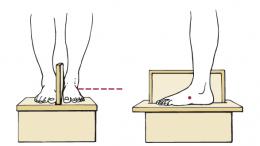

eest-taha suund seistes